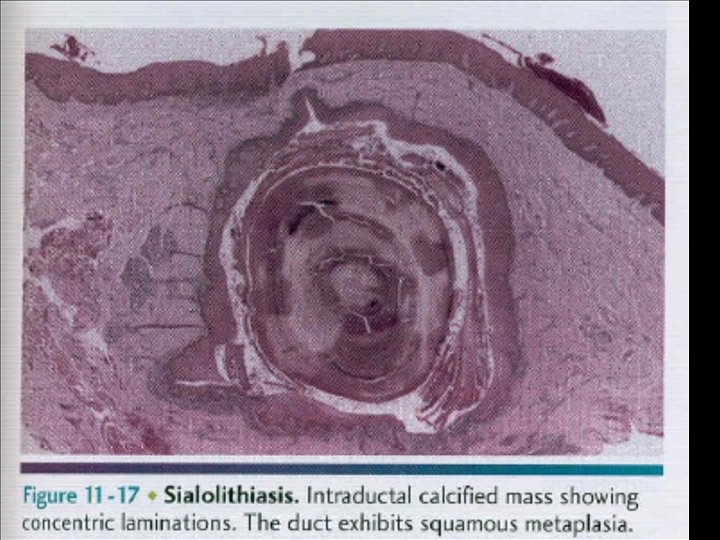

Obstructive SG Disorders: Sialolithiasis • A stone in the salivary duct or gland • Mechanical obstruction of the salivary duct • Major cause of unilateral diffuse parotid or submandibular gland swelling • Most frequent reason for submandibular gland resection

Sialolithiasis • The exact pathogenesis of sialolithiasis remains unknown. • Thought to form via…. an initial organic nidus that progressively grows by deposition of layers of inorganic and organic substances. • May eventually obstruct flow of saliva from the gland to the oral cavity.

Sialolithiasis § Acute ductal obstruction may occur at meal time when saliva producing is at its maximum, the resultant swelling is sudden and can be painful. § Gradually reduction of the swelling can result but it recurs repeatedly when flow is stimulated. § This process may continue until complete obstruction and/or infection occurs.

Stone Composition • Organic; often predominate in the center – Glycoproteins – Mucopolysaccharides – Bacterial products – Cellular debris • Inorganic; often in the periphery – Calcium carbonates & calcium phosphates in the form of hydroxyapatite